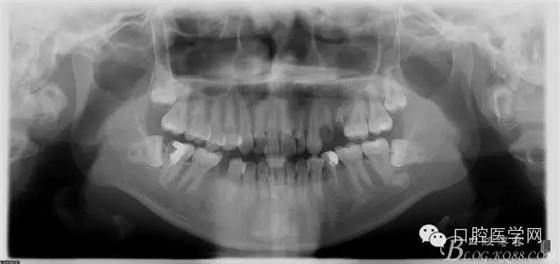

檢查前拍全景發(fā)現(xiàn)問題

根尖區(qū)低密度影像+根管欠充填